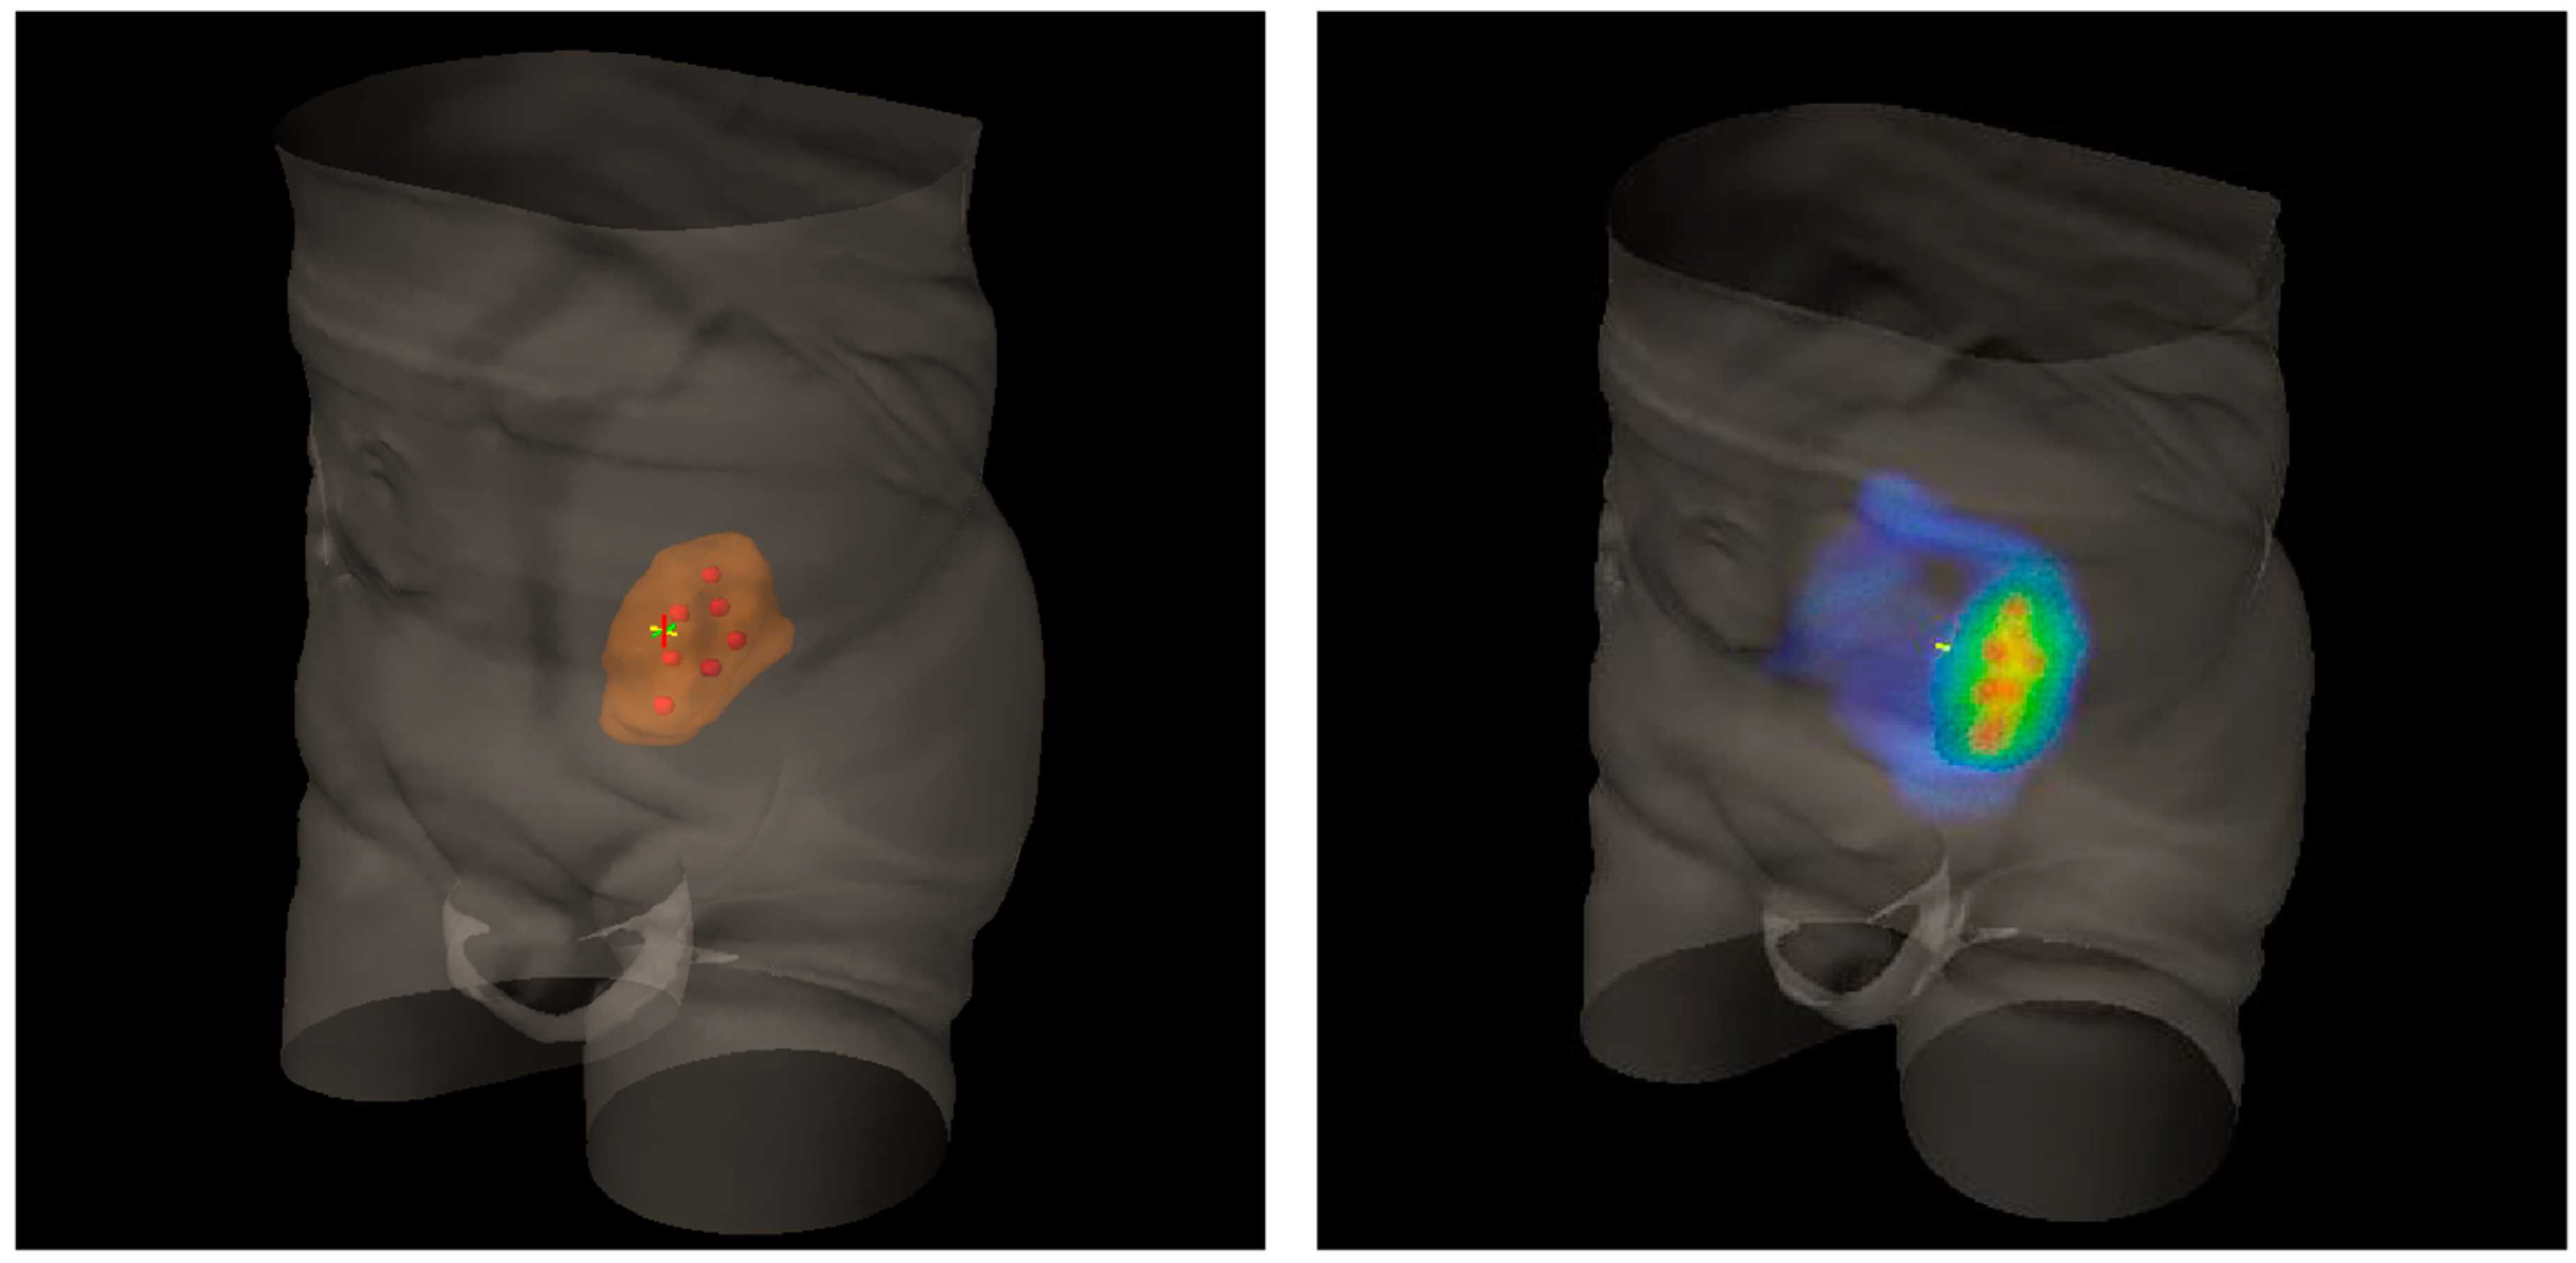

Figure 2.

Three-Dimensional (3D) rendering of bulky metastatic iliac lymph node packets from urothelial bladder cancer in a patient candidate for a salvage pelvic radiotherapy (on the left). On the right, 3D dose distribution with a lattice simulation approach. Blue is for the conventional standard dose, red for high peak ones.